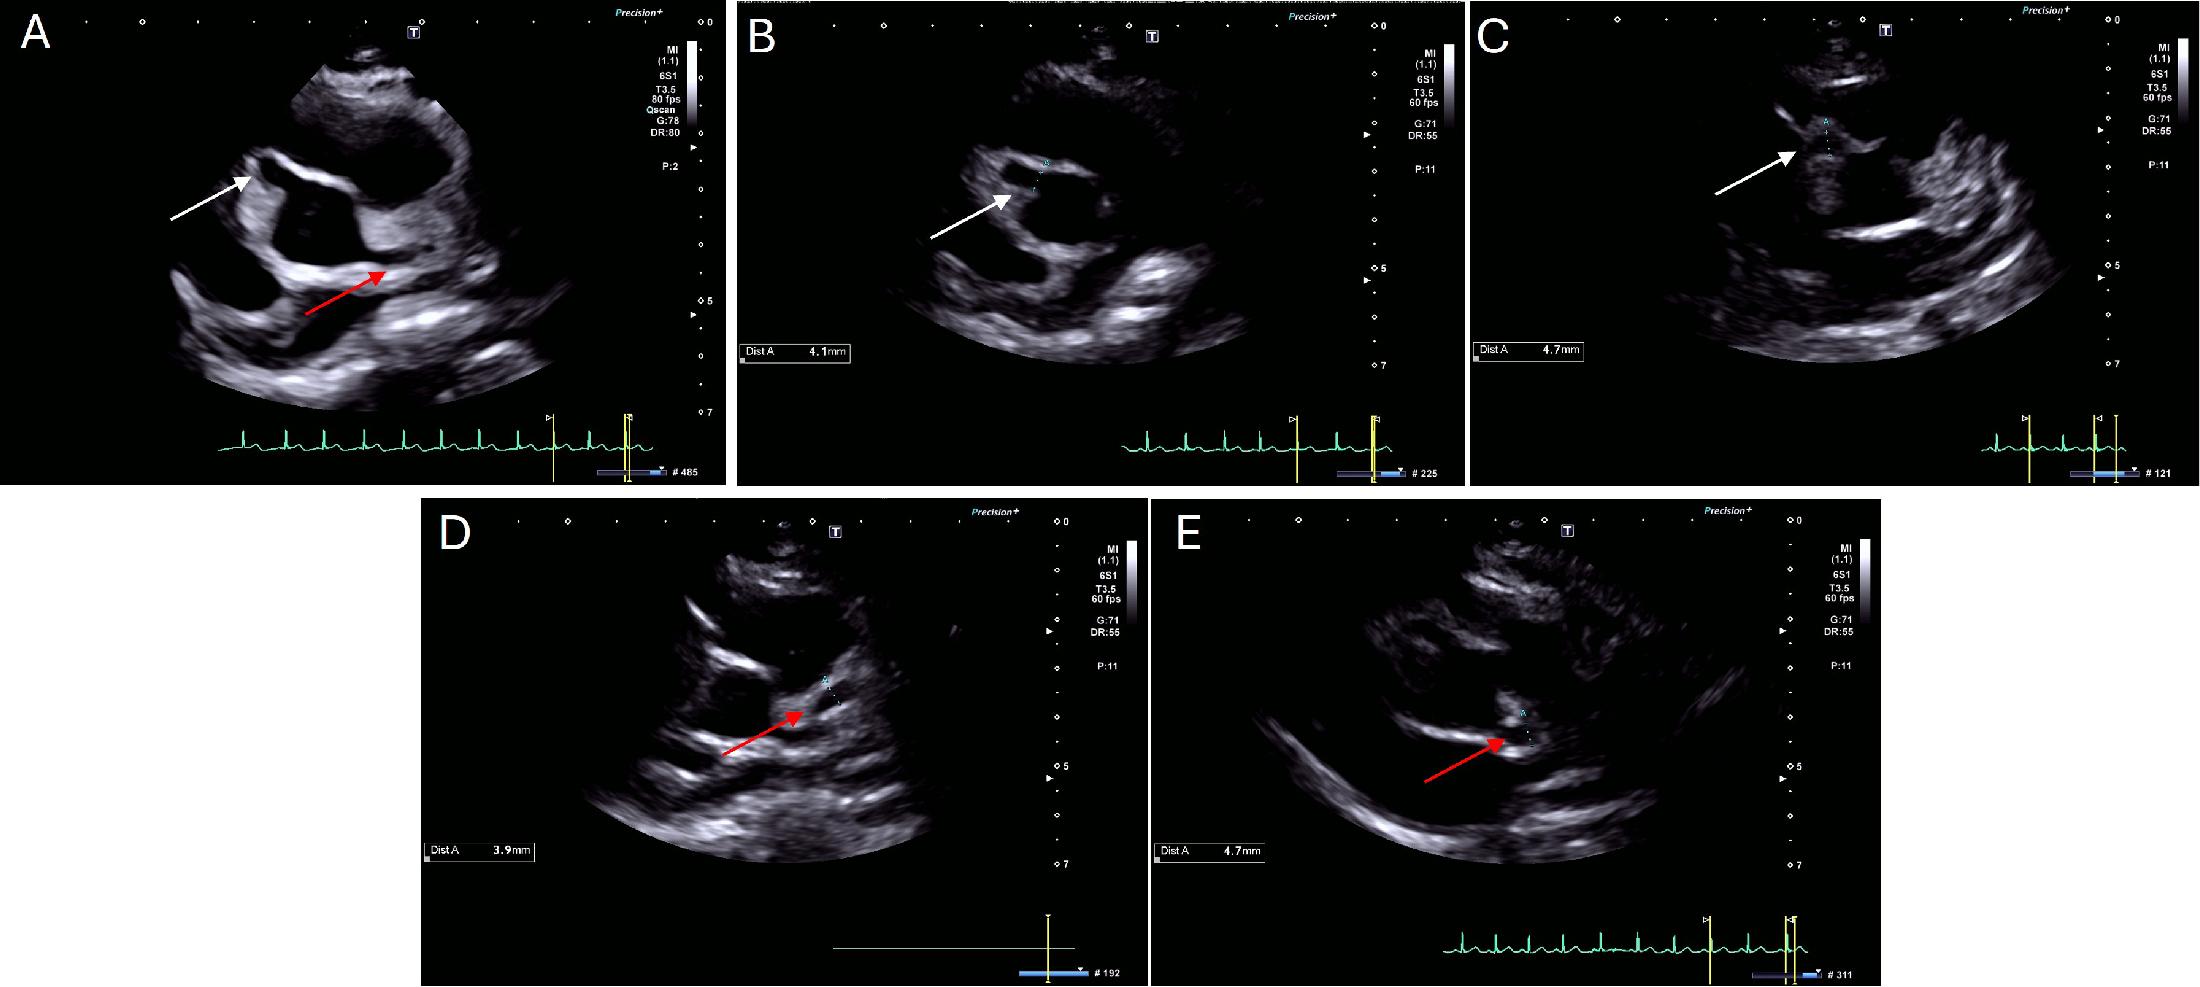

Figure 1